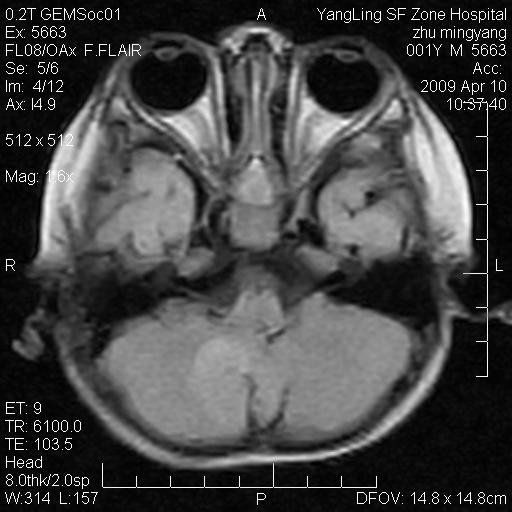

患者:1岁半,两天前外伤收住我院,ct检查小脑占位

考虑星形细胞瘤,建议增强

髓母细胞瘤或血管母细胞瘤,增强后可以鉴别;影像资料见 <。鱼博浪老师的《中枢神经系统ct与mr鉴别诊断》 小脑部肿瘤章节。

髓母细胞瘤或血管母细胞瘤!支持!

支持考虑髓母细胞瘤

考虑----髓母细胞瘤可能性大

考虑髓母细胞瘤或室管膜瘤。

支持髓母细胞瘤。

考虑髓母细胞瘤。

考虑髓母细胞瘤或星形细胞瘤

考虑髓母细胞瘤.

考虑髓母细胞瘤可能性大。

小脑肿瘤.考虑髓母细胞瘤可能.

就病灶部位及临床资料首先考虑髓母.